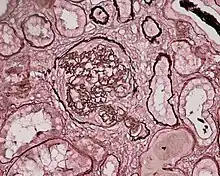

| Photomicrograph of a kidney biopsy from a person with crescentic glomerulonephritis showing prominent fibrocellular crescent formation and moderate mesangial proliferation in a glomerulus. Hematoxylin and eosin stain. | |

Rapidly progressive glomerulonephritis, also known as crescentic GN, is characterised by a rapid, progressive deterioration in kidney function. People with rapidly progressive glomerulonephritis may present with a nephritic syndrome. In management, steroid therapy is sometimes used, although the prognosis remains poor.[9] Three main subtypes are recognised:[4]: 557–558

Histopathologically, the majority of glomeruli present "crescents". Formation of crescents is initiated by passage of fibrin into the Bowman space as a result of increased permeability of glomerular basement membrane. Fibrin stimulates the proliferation of endothelial cells of Bowman capsule, and an influx of monocytes. Rapid growing and fibrosis of crescents compresses the capillary loops and decreases the Bowman space, which leads to kidney failure within weeks or months.